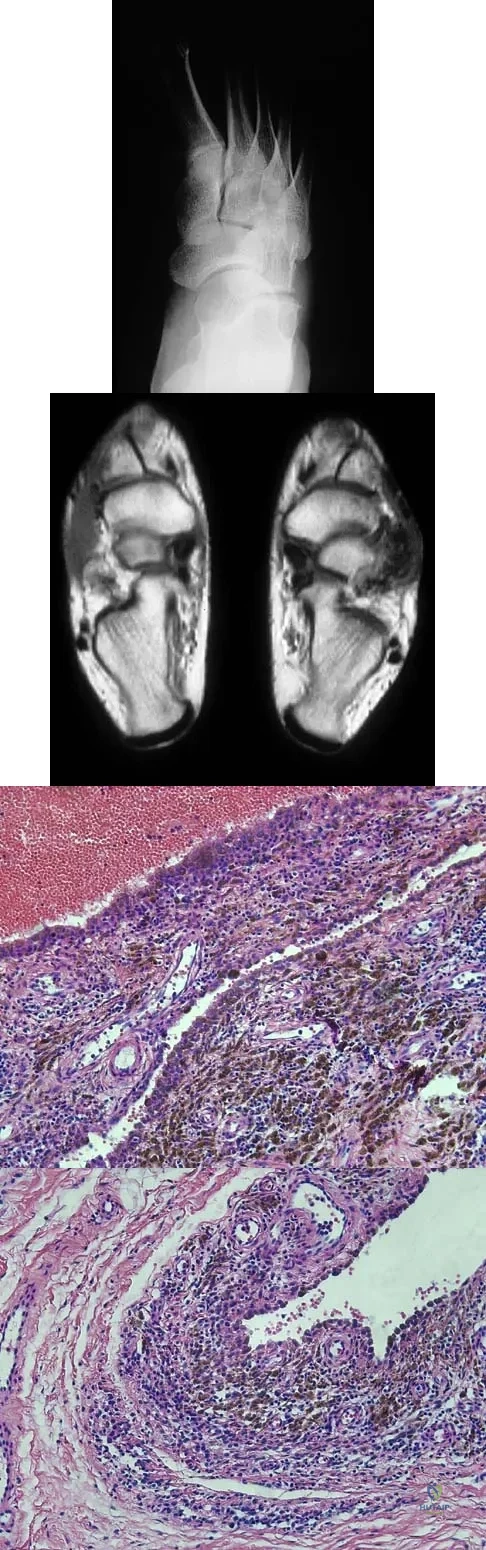

A 16-year-old girl has a painful foot mass. A radiograph, MRI scan, and biopsy specimens are shown in Figures 35a through 35d. What is the most likely diagnosis?

Explanation